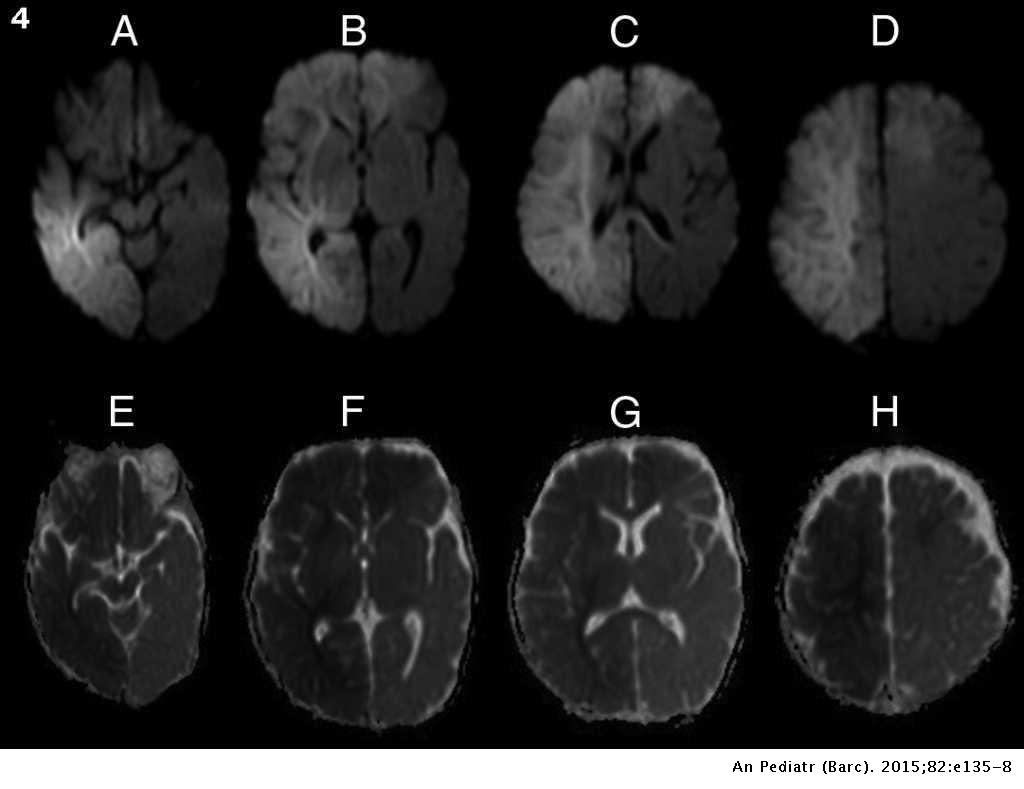

Traumatismo Craneal No Accidental A Proposito De Un Caso Anales De Pediatria